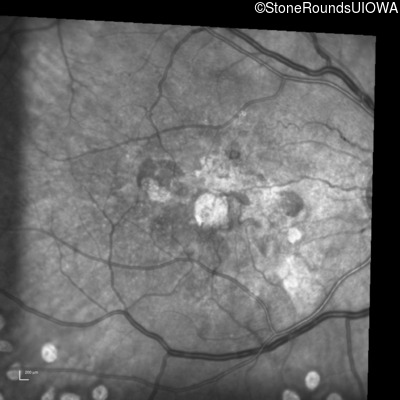

Visit at age: 60 years (Visit 2)

Infrared Fundus Photograph - Right - 20/100

Exemplar